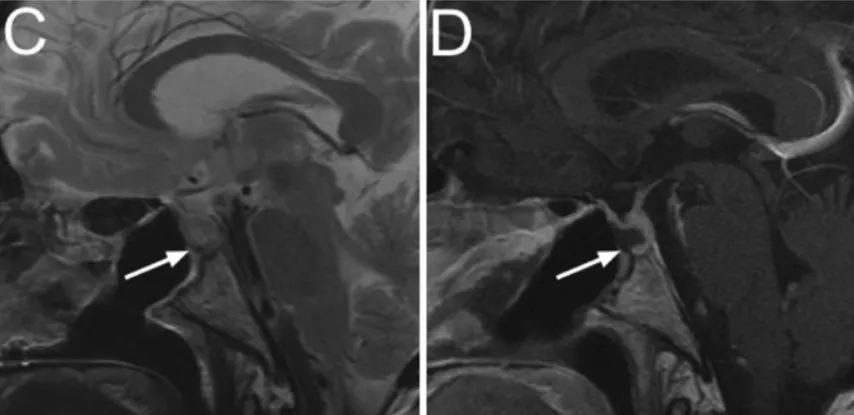

肿瘤切除后,为了重建鞍底,将PDS箔切割成在所有边缘与骨开口重叠约1-2mm的尺寸。然后将箔以轻微弯曲的方式置于硬膜外腔中鞍底骨边缘的下方。

C、D:术后即刻影像。矢状位T2WI(C)及T1WI(D)示PDS薄膜呈无信号带(箭头)。